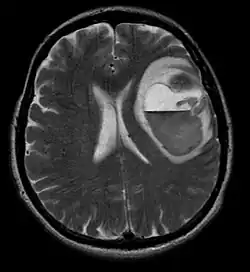

Durch Computertomographie (CT) und Kernspinresonanztomographie (MRT) kann eine Neoplasie im Gehirn effektiv nachgewiesen werden. Zur Identifizierung von Läsionen ist die MRT empfindlicher als die CT, weist aber für Patienten mit Herzschrittmachern, inkompatiblen Prothesen, Metallklammern und anderem Kontraindikationen auf. Die CT bleibt die Methode der Wahl, um Verkalkungen innerhalb der Läsionen oder Knochenerosionen der Schädeldecke oder -basis zu erkennen. Die Verwendung von Kontrastmitteln, die im Fall der CT jodiert und im Fall der MRT paramagnetisch (Gadolinium) sind, ermöglicht die Erfassung von Informationen über die Vaskularisation und Integrität der Blut-Hirn-Schranke, eine bessere Definition der Tumorgeschwulst im Vergleich zum umgebenden Ödem und die Erstellung von Hypothesen über den Grad der Malignität. Die radiologische Untersuchung ermöglicht auch eine Bewertung der mechanischen Auswirkungen und die daraus resultierenden Veränderungen der Gehirnstrukturen, die sich durch den Tumor ergeben, wie zum Beispiel Hydrocephalus und Hernien, deren Auswirkungen tödlich sein können. Schließlich kann mit dieser Diagnostik in Vorbereitung einer Operation der Ort der Läsion oder die Infiltration des Tumors in lebenswichtige Bereiche des Gehirns bestimmt werden. Zu diesem Zweck ist die MRT effizienter als die CT, da sie dreidimensionale Bilder liefern kann.[4]

Auf -Kernspintomogrammen erscheint ein intrakranieller Tumor als massive Läsion, die nach Verwendung des Kontrastmittels lumineszierender werden kann. Eine Signalanomalie gibt es jedoch immer in -Kernspintomogrammen, die auf das Vorhandensein einer Neoplasie oder eines vasogenen Ödems hinweist. Normalerweise ist eine stärkere Lumineszenz (Kontrastverstärkung) ein Hinweis auf einen Tumor höheren Malignitätsgrades. Ein Kontrastring ist charakteristisch für ein Glioblastom, wobei der Lumineszenzanteil dem lebenswichtigen Teil des bösartigen Tumors und der dunklere -hypointense Bereich der Gewebenekrose entspricht.[4]

Bei Diagnose und Behandlung dieser Läsionen wurden in jüngster Zeit erhebliche Fortschritte erzielt, wodurch das Überleben und die Kontrolle der Symptomatik verbessert wurden. Das Auftreten von Anzeichen und Symptomen ähnelt denen anderer massiver Läsionen im Gehirn. Das Diagnoseverfahren der Wahl ist die Kernspintomographie unter Verwendung von Kontrastmitteln.